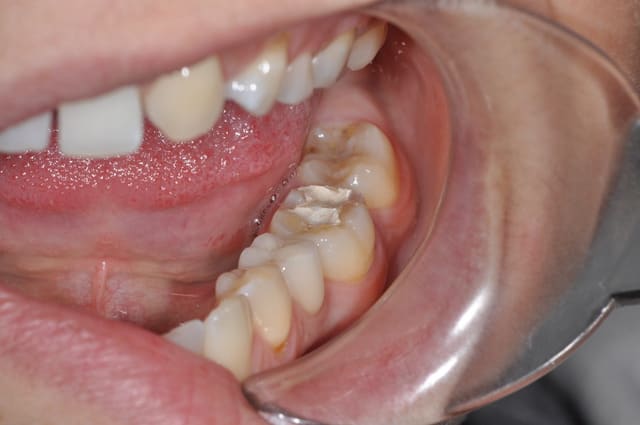

37 semble aussi abrasée, donc je soupconne une abrasion et des parafonctions

Je tenterais l'onlay . (+endo)

Je ne vois pas en quoi l'usure provoquée de 36 et l'usure soupçonnée sur 37 seraient des contre-indications . Tant qu'à avoir peur , l'implant lui même avec un problème occlusal général et des dysfonctions...ouin .

Je privilégierai l'inlay sauf si ça le fait pas une fois la carie nettoyée.

Il y a de bonnes parois dentaires, ça me ferait mal au coeur de les supprimer.

L'émail perdu complique un peu l'inlay-onlay.

1er choix inlay-onlay, 2e choix ccc, pas de tenon métal ou de IC.

Question pour ceux qui en ont fait plusieurs avec un peu de recul, dans le cas présenté, hormis la sous-occlusion, ça reste de l'inlay ou vous recouvrez la face occlusale ?